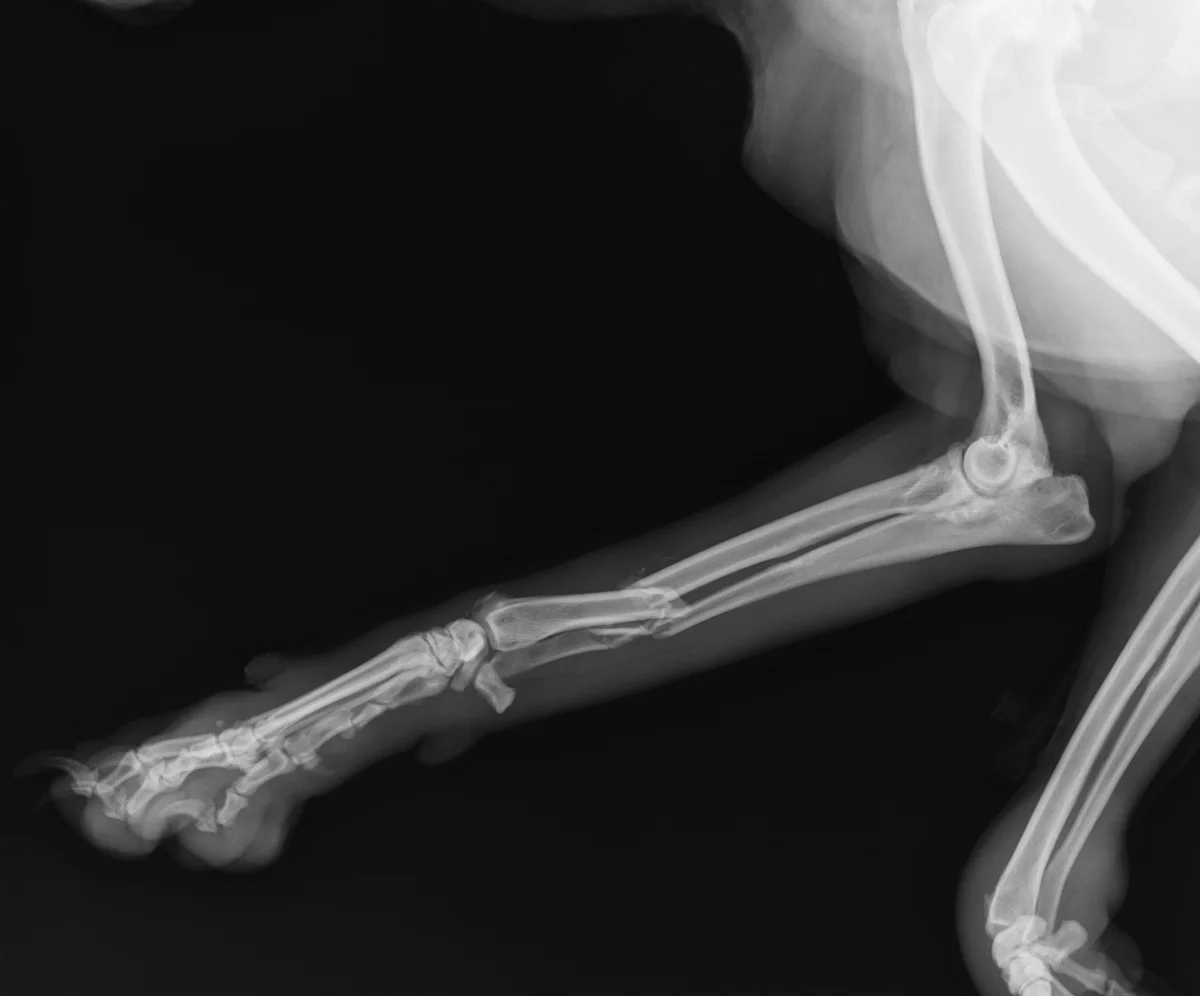

Radial fractures can be particularly challenging, requiring precise alignment and stabilization to support healing and function. See how you can better address the unique demands of these cases.